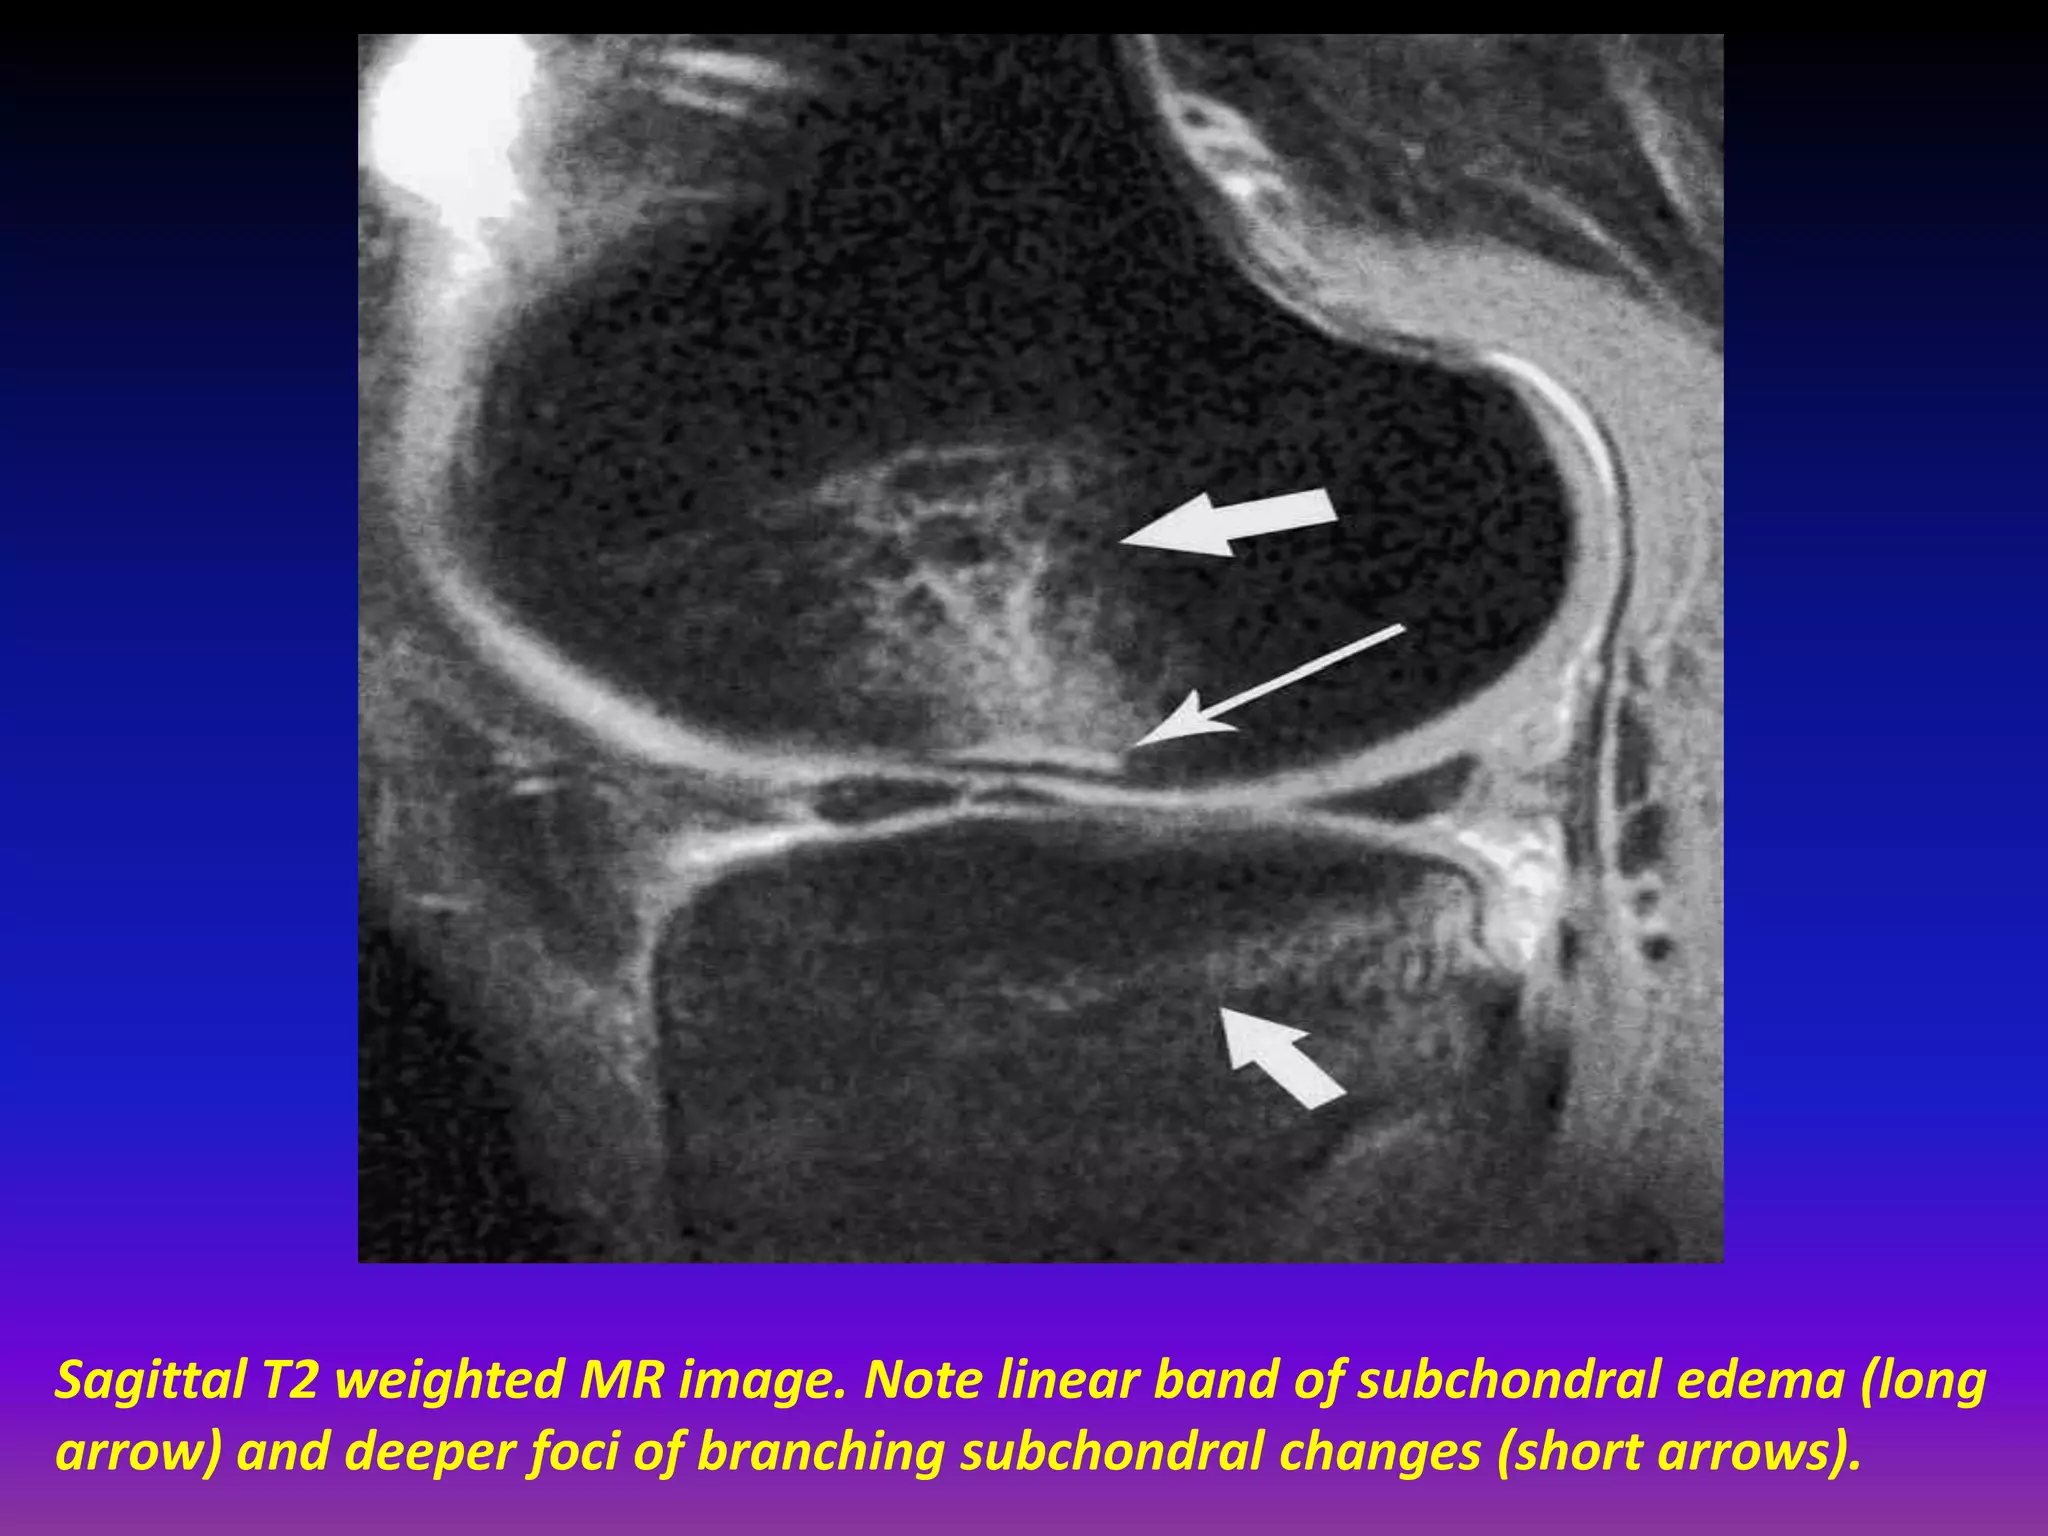

Sagittal T2 weighted MR image. Note linear band of subchondral edema (long

arrow) and deeper foci of branching subchondral changes (short arrows).

Sagittal T2 weightedMR image. Note linear band of subchondral edema (long arrow) and deeper foci of branching subchondral changes (short arrows).